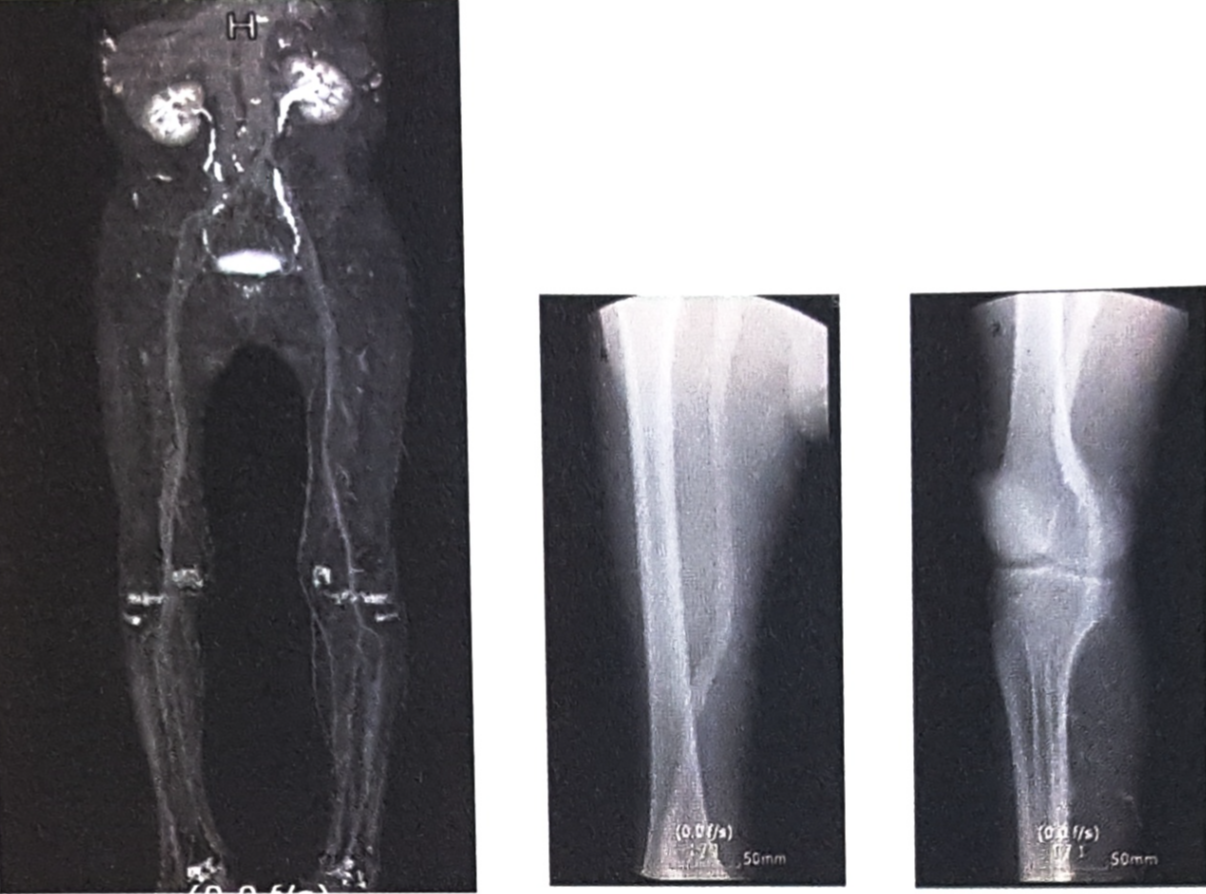

CT(Computed Tomography, 전산화단층촬영)검사는 신체의 일정 원하는 부위에서 단면을 깨끗한 2차원 영상으로 볼 수 있는 검사입니다. 촬영이 끝난 후 이러한 2차 단면영상을 컴퓨터를 이용하여 삼차원(3D)영상으로 재구성하면 동맥이 특별히 잘 보일 수 있도록 입체적인 영상도 얻을 수 있습니다.

목에 있는 경동맥